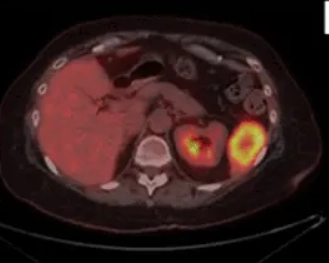

• Di căn lách (Splenic metastases)